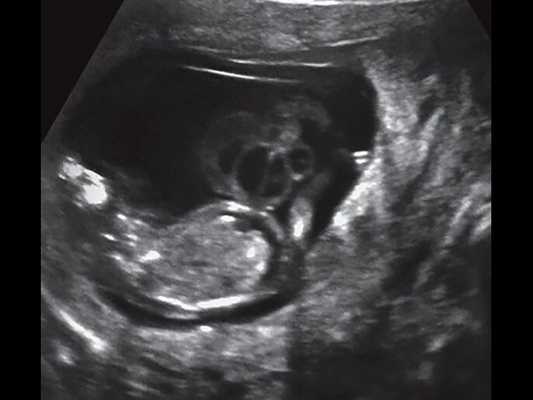

Пуповину легко можно визуализировать уже во 2 триместре беременности. Она хорошо определяется во время проведения ультразвукового обследования. Также посредством УЗИ доктор может оценить и состояние активно формирующейся плацентарной ткани. Во время обследования врач обязательно оценивает и то, как пуповина прикрепляется к плаценте.

Проще всего определить тип прикрепления пуповины к плаценте в том случае, если плацентарная ткань располагается по передней или боковой стенке матки.

Если по каким-то причинам плацента расположена на задней стенке, то в таком случае определить тип прикрепления становится гораздо сложнее. В таком случае проводить обследования лучше на аппаратах экспертного уровня. Это позволяет получить более информативные и точные результаты.